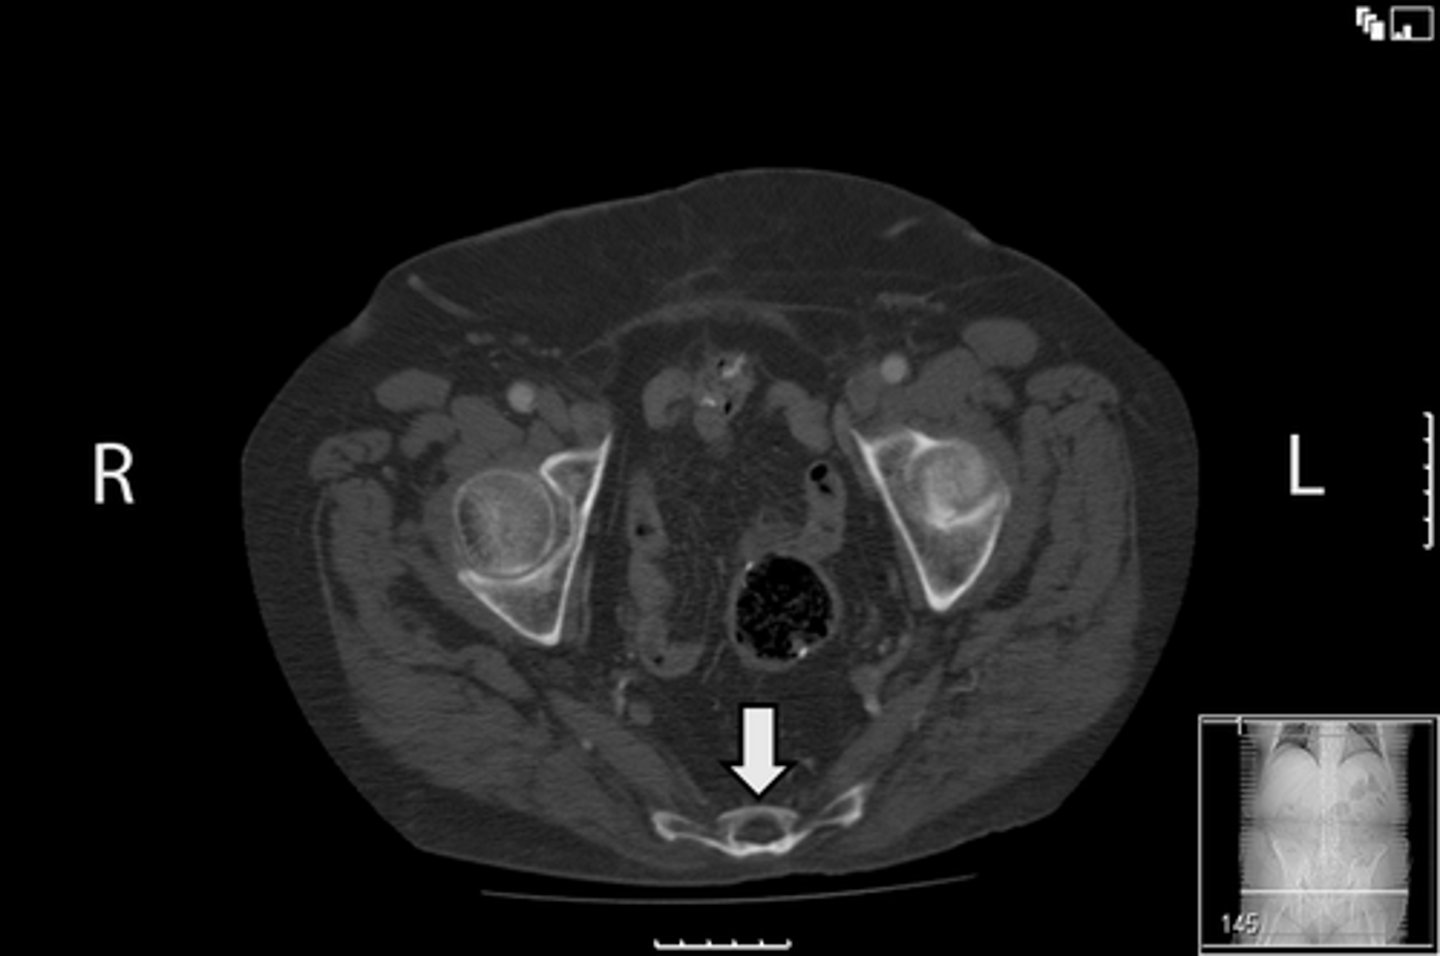

Axial bony pelvis CT

What is the image?

<p>What is the image?</p>

38

New cards

L acetabulum

What is indicated in the image?

<p>What is indicated in the image?</p>

39

L femoral head

40

L piriformis muscle

41

R femoral head

42

R piriformis muscle

43

R acetabulum (posterior part)

44

Sacrum